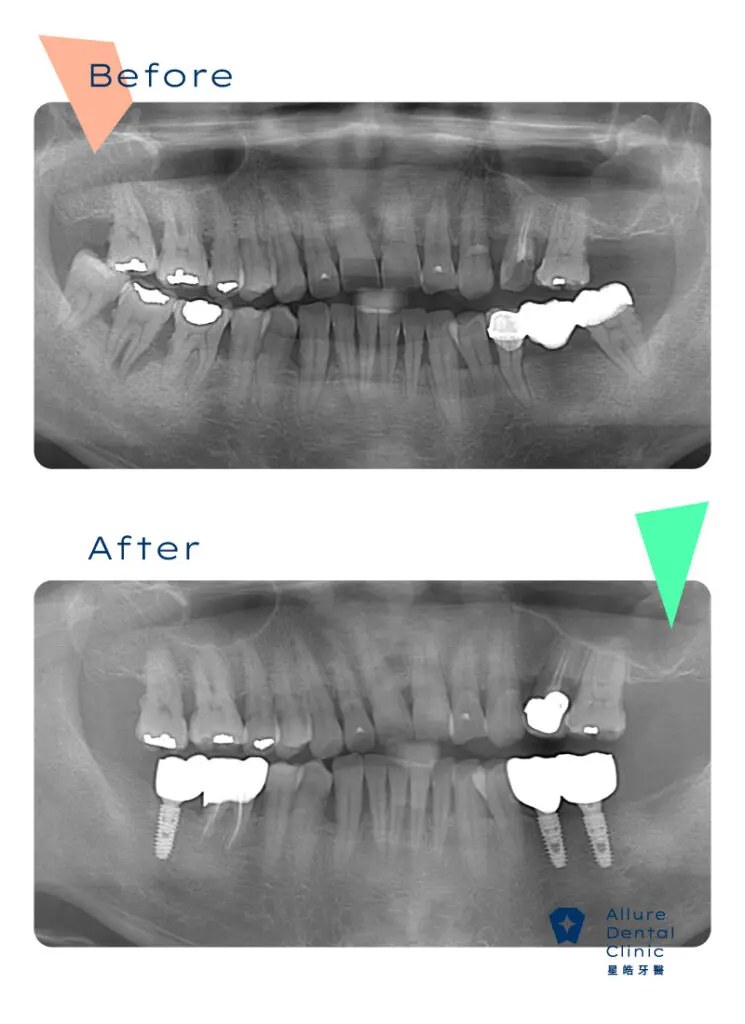

全口重建案例4

主治醫師:副院長 林禹書 醫師